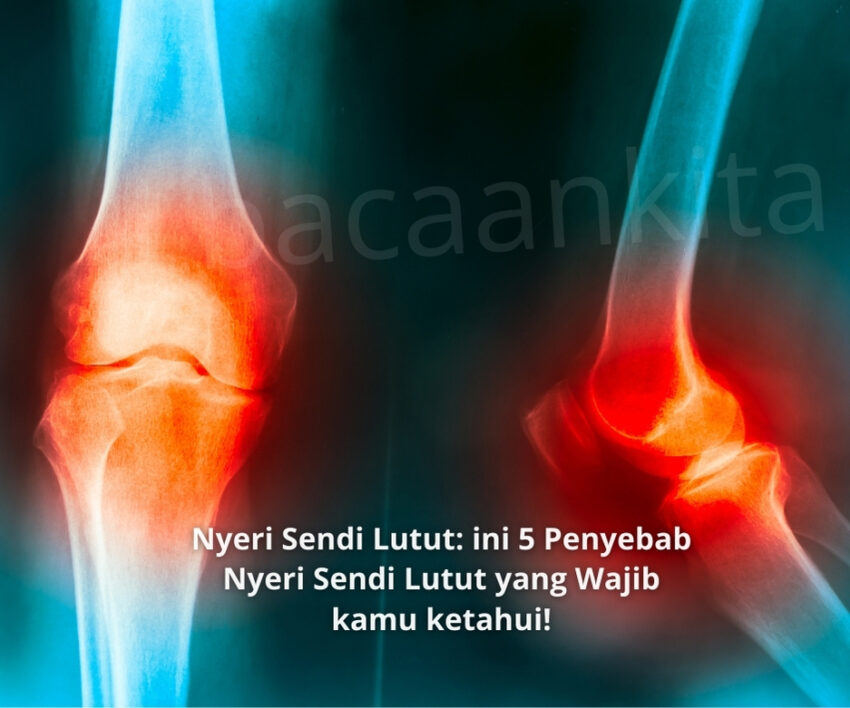

Apa Itu Nyeri Sendi Lutut?

Nyeri sendi lutut adalah kondisi yang bisa bikin siapa aja bete, dari anak muda sampai orang tua. Sakit di area lutut ini bisa muncul karena berbagai faktor, mulai dari cedera ringan sampai penyakit serius seperti osteoarthritis. Masalah ini nggak boleh dianggap remeh, apalagi kalau sudah sampai mengganggu aktivitas sehari-hari.

Penyebab Nyeri Sendi Lutut

Banyak faktor yang bisa jadi biang keladi sakit lutut. Nah, berikut beberapa penyebab utama yang sering terjadi: